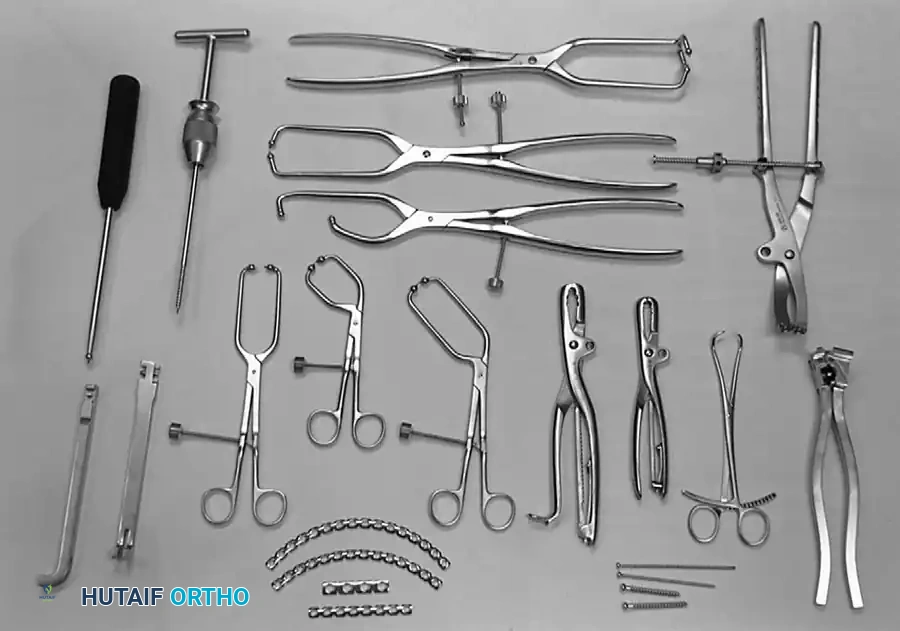

SURGICAL APPROACHES AND POSITIONING

Selecting the correct surgical approach is the most critical decision in acetabular fracture surgery. The approach is dictated by the fracture pattern, the column requiring the most manipulation, and the presence of soft tissue injuries.

The Kocher-Langenbeck Approach

- Indications: Posterior wall, posterior column, and certain transverse fractures.

- Positioning: Prone or lateral decubitus. Prone positioning allows for easier reduction of the posterior column using gravity, while lateral positioning is preferred if the patient has severe pulmonary contusions or requires simultaneous access to the anterior column.

- Interval: The gluteus maximus is split in line with its fibers. The short external rotators (piriformis, obturator internus, gemelli) are tagged and released at their femoral insertions to expose the retroacetabular surface and the greater sciatic notch.

- Nerve Protection: The sciatic nerve must be identified and meticulously protected throughout the procedure. Keeping the hip extended and the knee flexed reduces tension on the nerve.

The Ilioinguinal Approach

- Indications: Anterior column, anterior wall, and anterior-dominant both-column fractures.

- Positioning: Supine on a radiolucent table.

- Technique: This is an entirely extrapelvic approach that utilizes three distinct surgical windows to access the anterior column from the SI joint to the pubic symphysis.

- Lateral Window: Between the iliac crest and the iliopsoas muscle.

- Middle Window: Between the iliopsoas/femoral nerve and the external iliac vessels.

- Medial Window: Medial to the external iliac vessels and lateral to the rectus abdominis.

- Biomechanics: This approach allows for the placement of long reconstruction plates along the pelvic brim (iliopectineal line) to buttress the anterior column.

The Modified Stoppa Approach

- Indications: Medial displacement of the quadrilateral surface, anterior column fractures, and certain both-column fractures.

- Positioning: Supine.

- Technique: A transverse Pfannenstiel incision is made, and the surgeon works intrapelvically, deep to the rectus abdominis and along the pelvic brim. This approach provides direct visualization of the quadrilateral plate and allows for the application of medial buttress plates to prevent medial subluxation of the femoral head. It is frequently combined with a lateral window (from the ilioinguinal approach) for complete anterior column access.